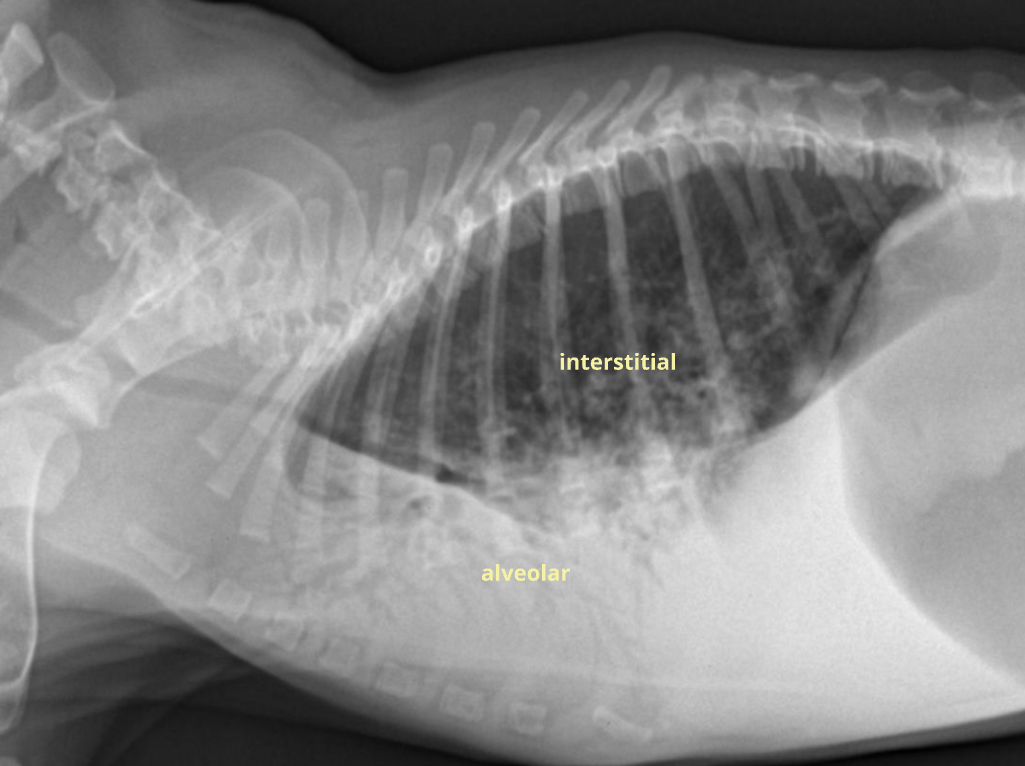

| โณ๏ธ Alveolar pattern |

| Fluid, blood, cell ๋ฑ์ด ๊ท ์งํ๊ฒ ์ฐจ ์์ * interstitial pattern์ ๋นํด ์งํ๊ณ ๊ท ์งํจ. |

| Radiographic sign - Consolidation (ํ๊ฒฝํ; ๊ณต๊ธฐ ์ธ ๋ค๋ฅธ ๊ฒ ์ฐธ) - Lobar sign (์ฝ๊ณผ ์ฝ ์ฌ์ด ๊ฒฝ๊ณ๊ฐ ๋๋ฌ๋จ) - Air bronchogram; โTrees in the fogโ (ํ์ฝ์ด ์ฐจ์ ๊ธฐ๊ด์ง๊ฐ ๋๋ฌ๋จ) - Cardiac effacement |

| DDx Pneumonia Edema Pulmonary hemorrhage Atelectasis (๋ฌด๊ธฐํ) Mass Torsion, infarct |

| โณ๏ธ Interstitial pattern |

๋ฒฝ์ด ๋๊บผ์์ง๊ณ ๊ณต๊ธฐ๊ฐ ์ฐจ๋ฉด์ ์ง์ ๋ถํ๊ฒ ๋ํ๋๋ ๋ชจ์.![]() |